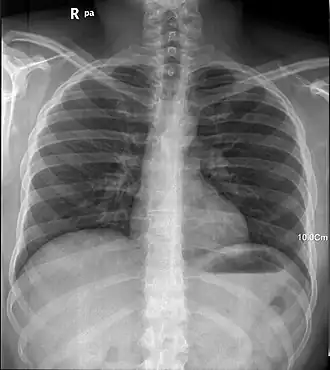

Рентген легких человека

Рентгенограмма грудной клетки человека (прямая передняя проекция).